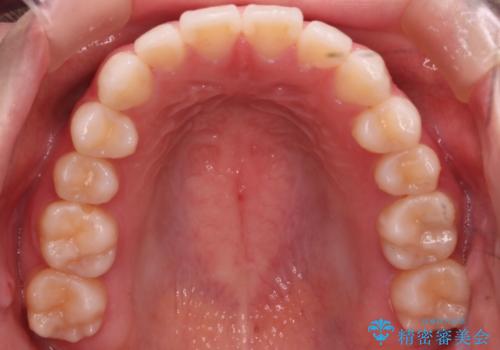

【審美装置】前歯で噛めない!抜歯しないで治したい

- 前歯の捻転とかみ合わせを主訴に来院されました。今回は抜歯をせずにIPRを実施し、並べる計画を立てました。

ワイヤー矯正を行いながら、顎間ゴムを患者さまにご協力していただき、短い期間で終了できました。